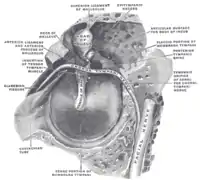

Martillo visible en el centro. | ||